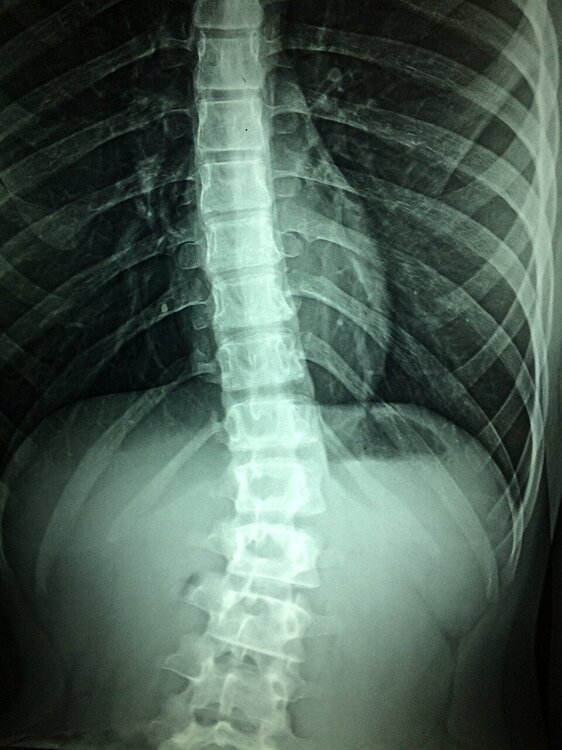

Omurilik yaralanmasını onarmak için kırmızı ışık terapisi müthiş bir ilerleme kaydetti

Omurilik yaralanması (SCI) olan hastalar, kırmızı ve yakın kızılötesi ışık kullanılarak sinir bağlantılarının onarılmasına yönelik gelecekteki bir tedaviden yararlanabilirler.

Birleşik Krallık'taki Birmingham Üniversitesi'ndeki bilim insanları tarafından icat edilen ve Birmingham Enterprise Üniversitesi tarafından patenti alınan yöntem, ışığın doğrudan yaralanma bölgesine iletilmesini içeriyor.